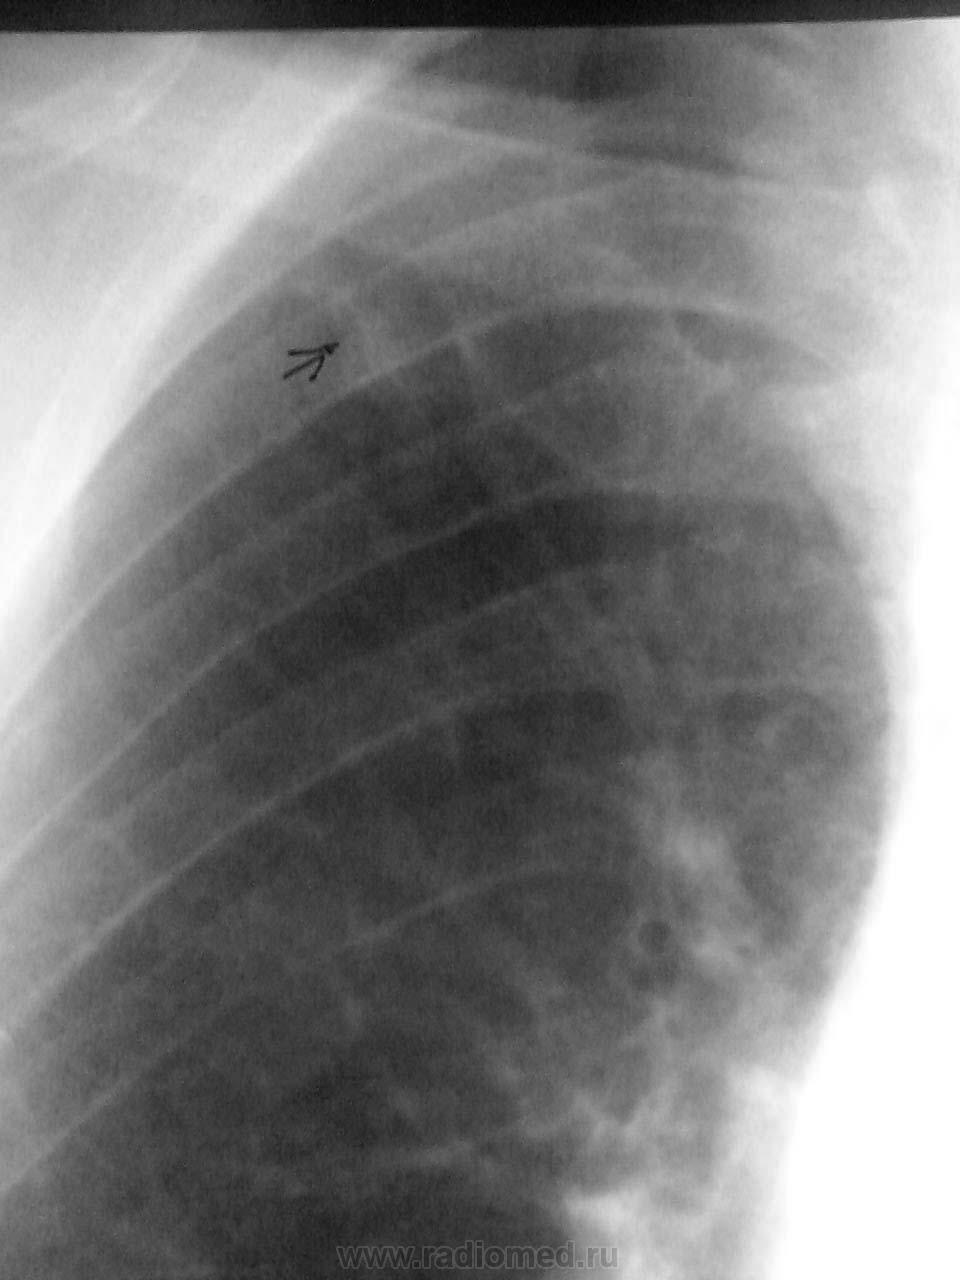

Мужчина 1952 г.р.Рентгенологическое исследование от 4.10.13. Жалоб не предъявлял. Выявлен при профосмотре.За предыдущие годы - норма.Рентгенкартина не впечатлила. Фиброз - он и в Африке

фиброз.Видали и похлестче. Может пневмонией переболел.

Но, так как изменения выявлены впервые, решила проконтролировать. Пригласила на рентгенконтроль через 3 месяца. Позже,но пришёл. Вот динамика.

Прошу извинить. Совсем не фиброзная скиалогия... Дообследовать ведь можно было и раньше, то есть тогда. Но что уж теперь - процесс расцвёл... (по нашей вине) как всегда.(

Тени плотность не столь велика, чтобы фиброзом называться могла.)

Несмотря на невысокое качество снимков, смотрится тень как инфильтрат. А если немного поработать в цифре, то начинает маячить и тень за 7 ребром... Пропуск. Так бывает. Печально. Но факт...

К сожалению, это не цифра, а плёнка. Подработать не получается. Качество изображения ухудшилось ещё и при съемке телефоном.Часть изображений для демонстрации обработала в Фотошопе (инверсия -  негатив превращает в позитив)  В натуре на первых снимках всё выглядит вполне линейно и достаточно чётко, что и усыпило бдительность. Я себя не оправдываю. Но пусть мой пример будет другим наука.